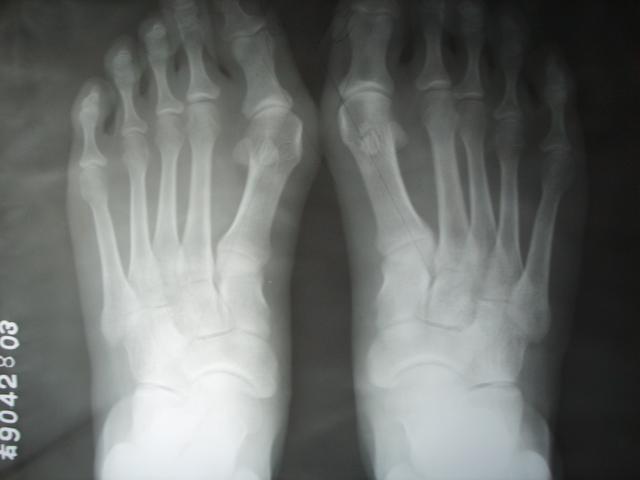

一、足在负重时其前后位的 X光片变化是第一跖骨与近节趾骨的成角即外翻角 ,第一 二跖骨纵轴之夹角称跖骨角,也称跖间角。

大脚骨X线情况

二、拇趾向外侧偏斜,第一跖骨内翻,跖骨头内侧呈赘样突起,并形成第一跖趾关节创伤性关节炎及半脱位,这些都是大脚骨发病的特点。

中度拇外翻